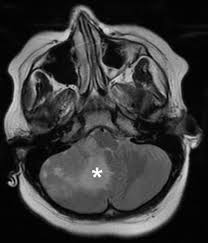

Facts About Brain Tumours Brain Tumour Foundation Of Canada from www.braintumour.ca These are four words no parent ever wants to hear. For example, if a brain tumor is located in the cerebellum at the back of the head, a child may have trouble with movement, walking, balance and coordination. Changes in memory or thinking This is important if your child becomes ill and you have questions or need advice. Signs or symptoms vary depending on a child's age and the location of the tumor, but may include: Having your child diagnosed with a terminal brain tumour is one of the most devastating and terrifying things that can happen to any parent. Some children may know or have heard about a person who has died from cancer. In some children, seizures are the first symptom of a brain tumor.

Having your child diagnosed with a terminal brain tumour is one of the most devastating and terrifying things that can happen to any parent. Balance and walking problems trouble. I have to look up the time and date because my brain refuses to acknowledge this information, it's automatically sent. In some children, seizures are the first symptom of a brain tumor. A brain tumor can cause symptoms by directly pressing on the surrounding parts of the brain that control certain body functions, or by causing a buildup of spinal fluid and pressure throughout the brain (a condition known as hydrocephalus).

This way you will be able to address questions that your child may have about your cancer diagnosis. When you have a child with cancer, social media can provide a wonderful lifeline of support. If you think your child might be experiencing some potential warning signs of cancer we encourage you to make an appointment with the child's pediatrician as a first step. Talking with your children about a brain tumor diagnosis www.abta.org. These are four words no parent ever wants to hear. For example, if a brain tumor is located in the cerebellum at the back of the head, a child may have trouble with movement, walking, balance and coordination. A brain tumor can cause symptoms by directly pressing on the surrounding parts of the brain that control certain body functions, or by causing a buildup of spinal fluid and pressure throughout the brain (a condition known as hydrocephalus). I have to look up the time and date because my brain refuses to acknowledge this information, it's automatically sent. Other conditions that cause fatigue include autoimmune diseases, neurological conditions,. And if your child starts asking questions about their illness, it can be desperately difficult to know what to say. By the time stage 4 has been reached, probably one or more of three treatments has been attempted: Your child may have any of the following: Each treatment, while aimed at removing the cancer, can affect normal brain function.